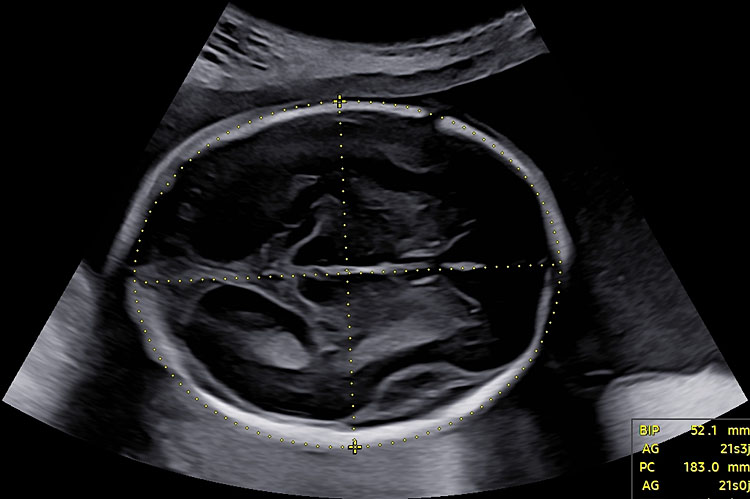

Ellipse

AC :

measurements